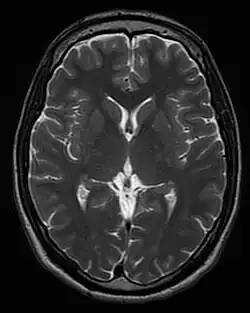

| T2 weighted | T2 | Measuring spin–spin relaxation by using long TR and TE times |

Standard foundation and comparison for other sequences |

T1 and T2

Each tissue returns to its equilibrium state after excitation by the independent relaxation processes of T1 (spin-lattice; that is, magnetization in the same direction as the static magnetic field) and T2 (spin-spin; transverse to the static magnetic field). To create a T1-weighted image, magnetization is allowed to recover before measuring the MR signal by changing the repetition time (TR). This image weighting is useful for assessing the cerebral cortex, identifying fatty tissue, characterizing focal liver lesions, and in general, obtaining morphological information, as well as for post-contrast imaging. To create a T2-weighted image, magnetization is allowed to decay before measuring the MR signal by changing the echo time (TE). This image weighting is useful for detecting edema and inflammation, revealing white matter lesions, and assessing zonal anatomy in the prostate and uterus.

The standard display of MRI images is to represent fluid characteristics in black and white images, where different tissues turn out as follows: